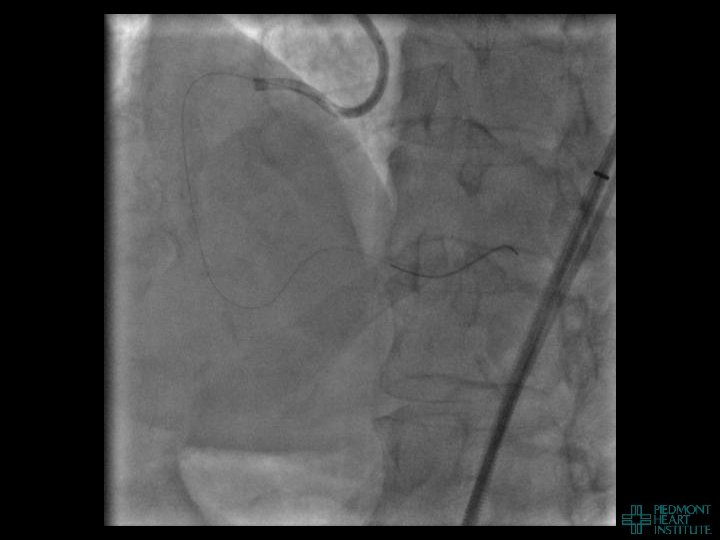

Coronary Perforation Methods of Patient Management • Dual Catheter (‘Ping Pong’) Technique • Prolonged

Coronary Perforation Methods of Patient Management • Dual Catheter (‘Ping Pong’) Technique • Prolonged balloon inflation and covered stents • Reversal of anticoagulation — Know contradictions to protamine sulfate for UFH; Avoid bivalirudin, LMWH — Reserve GP 2 b 3 a inhibition until successful crossing and wire change-out Embolization • — Coil, gelfoam, methacrylate, autologous blood/fat • Microcatheter Occlusion • Confirmation of successful management — Contralateral injection — Right heart catheterization — Echocardiogram — Contrast echocardiography